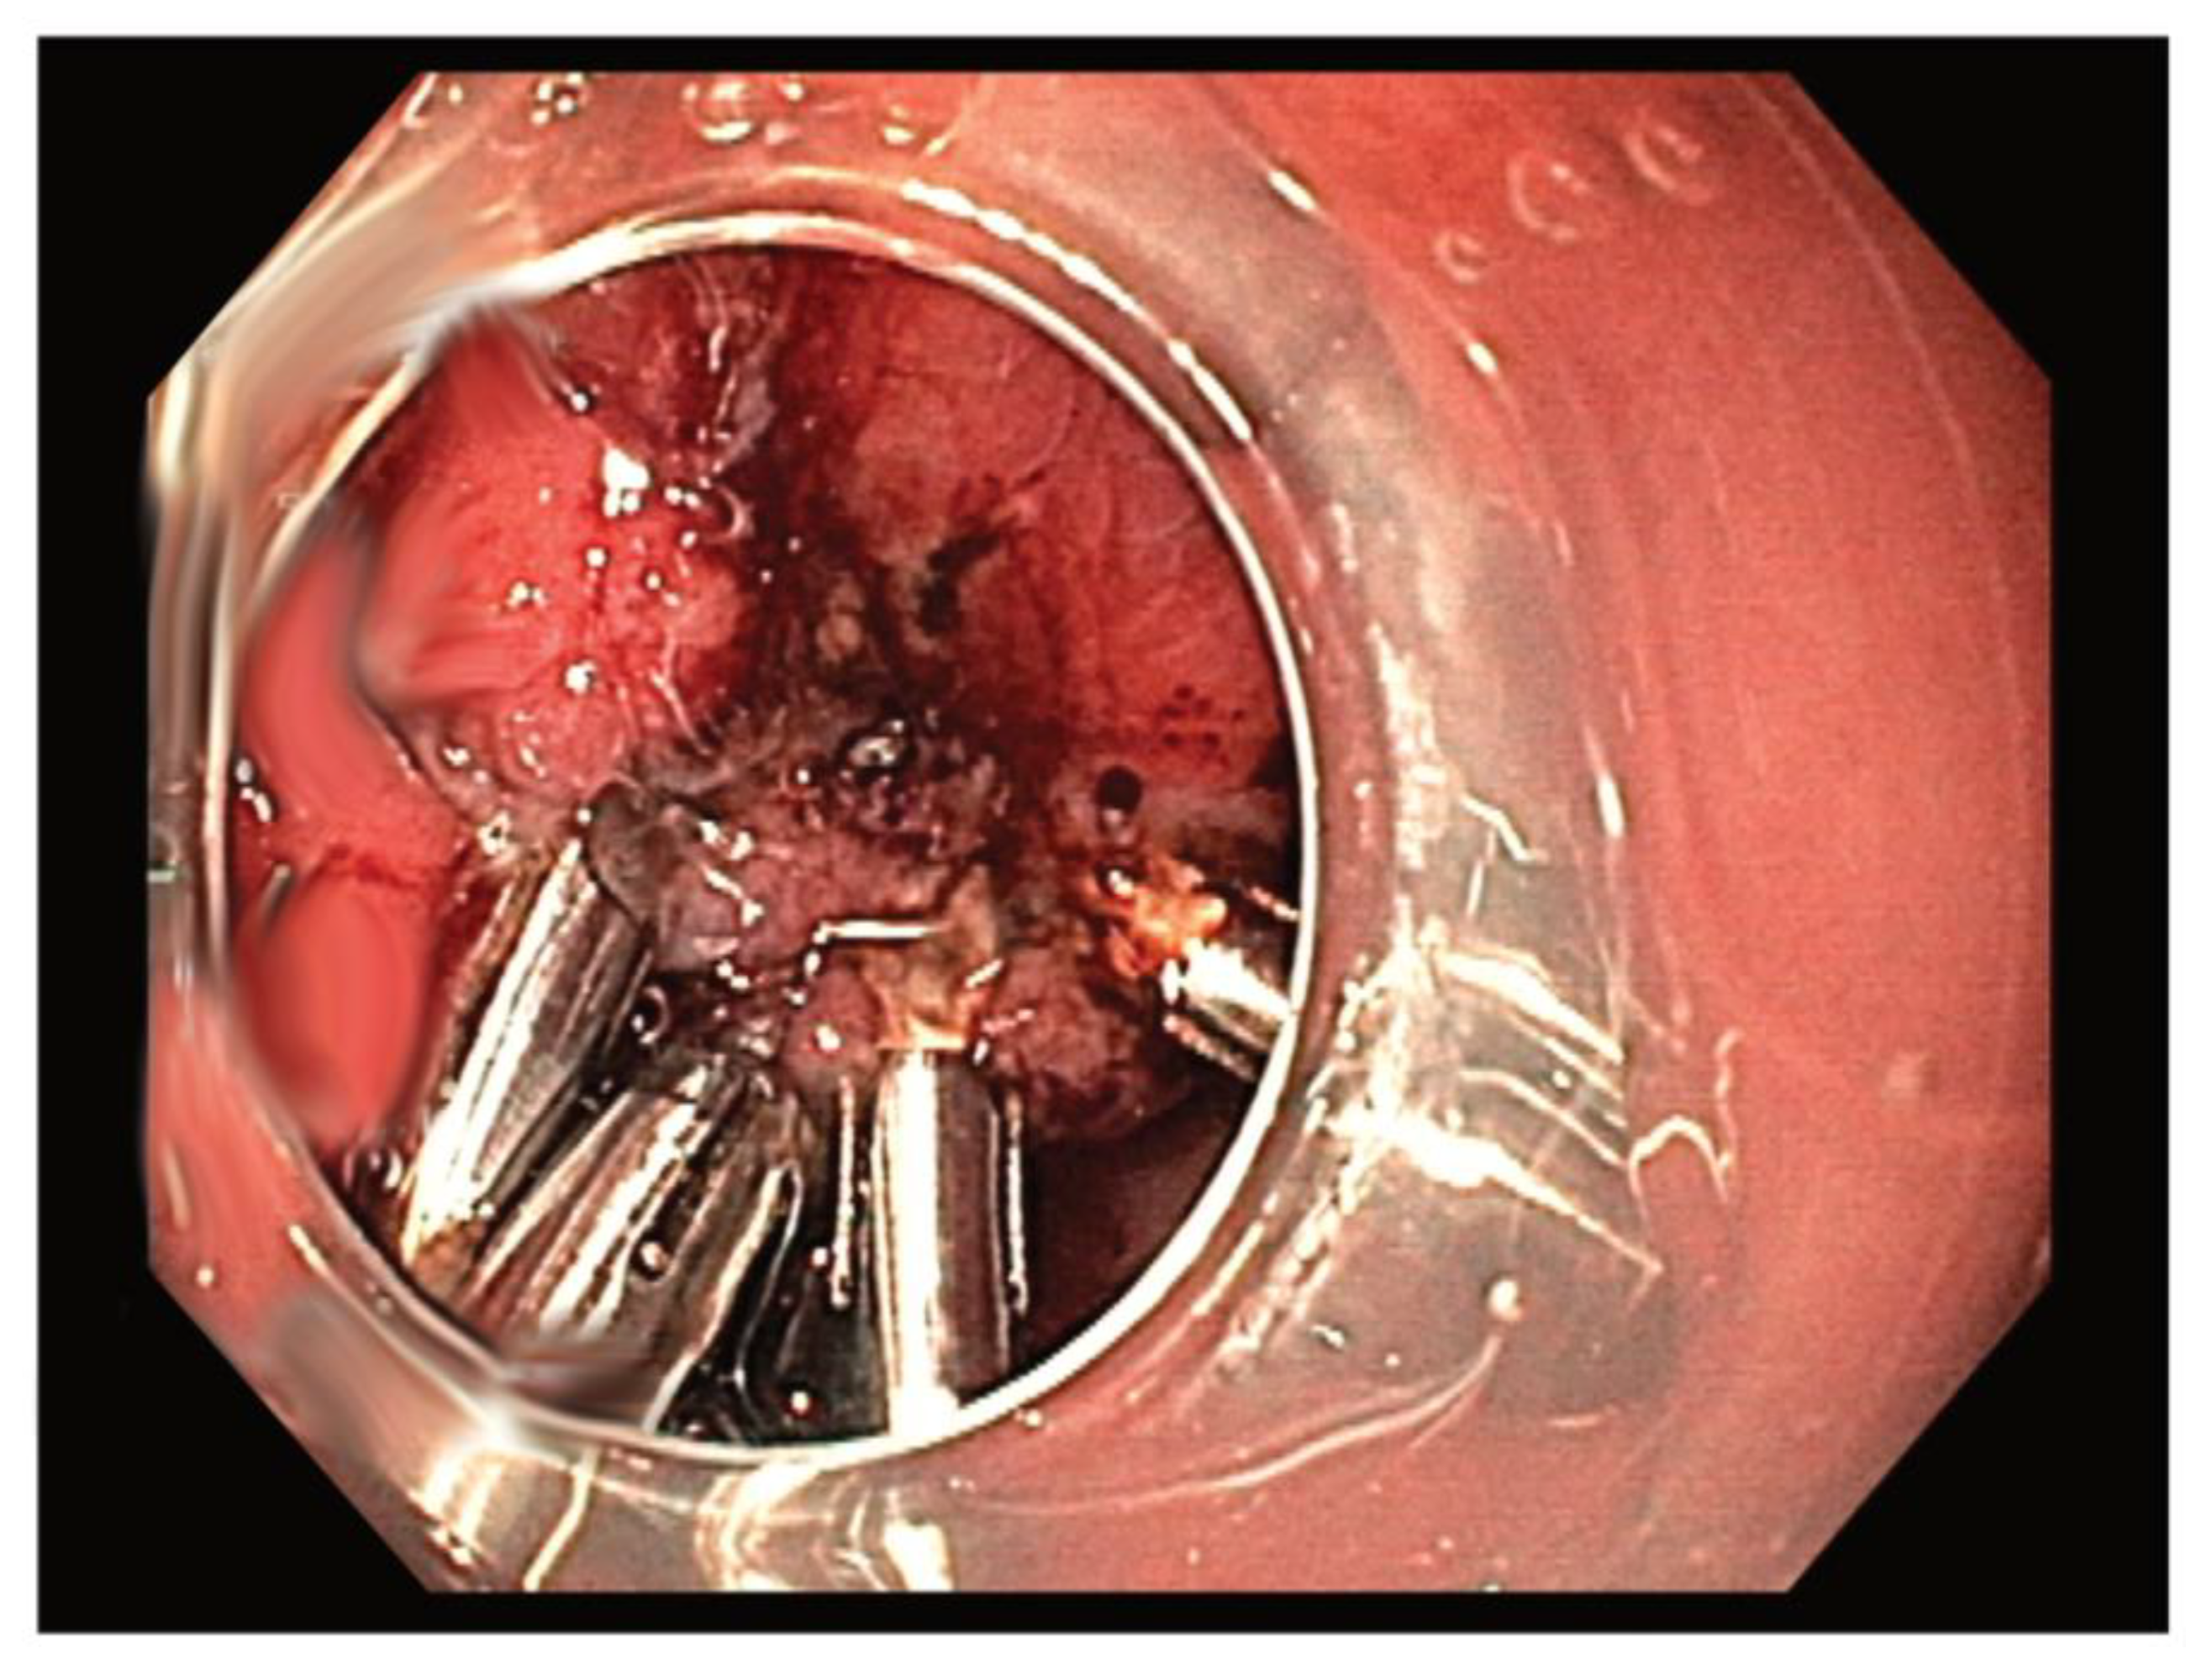

- The less invasive procedure includes various endoscopic resection techniques, such as ESD, EFTR, and STER.

- The hybrid technique combining endoscopic resection and endoluminal suturing appears to be a potential alternative for selected gastric GISTs with a large size and a high MP connection grade (type > I), with advantages over ESD.